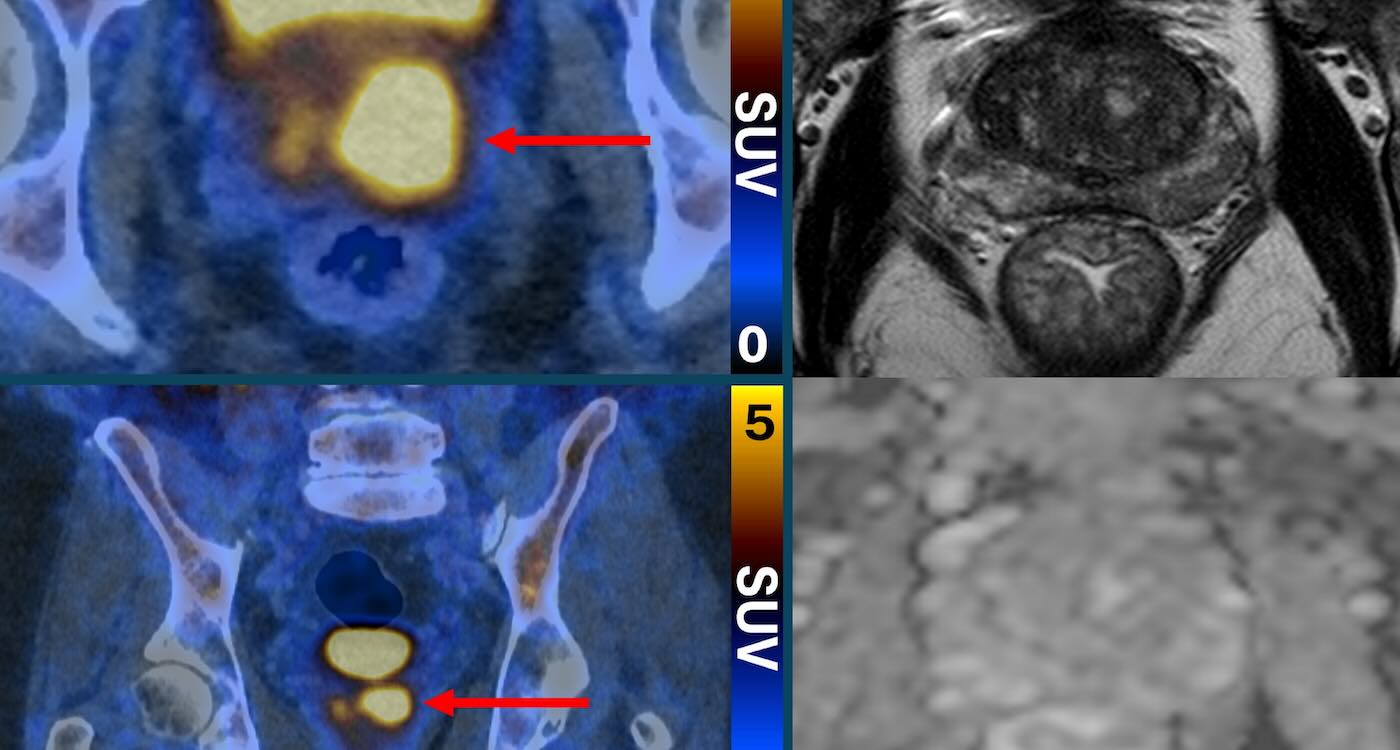

Scans that make prostate cancer cells ‘glow’ can eliminate the need for invasive biopsies—and they are already available in Australia and Europe. The state of the art imaging test uses a molecule that binds to prostate cancer cells, causing them to “light up in a remarkable way”—appearing as bright spots in the scanning image. The […]